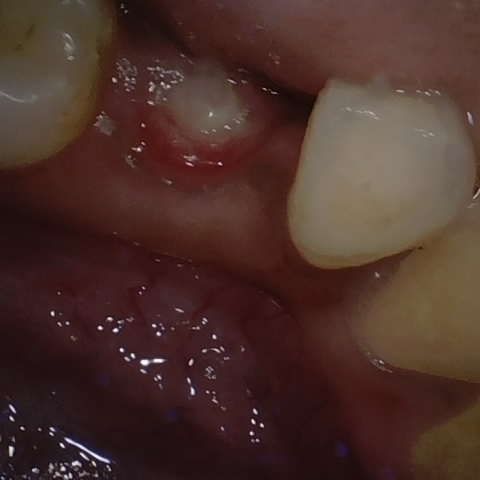

Annotated as "Good"